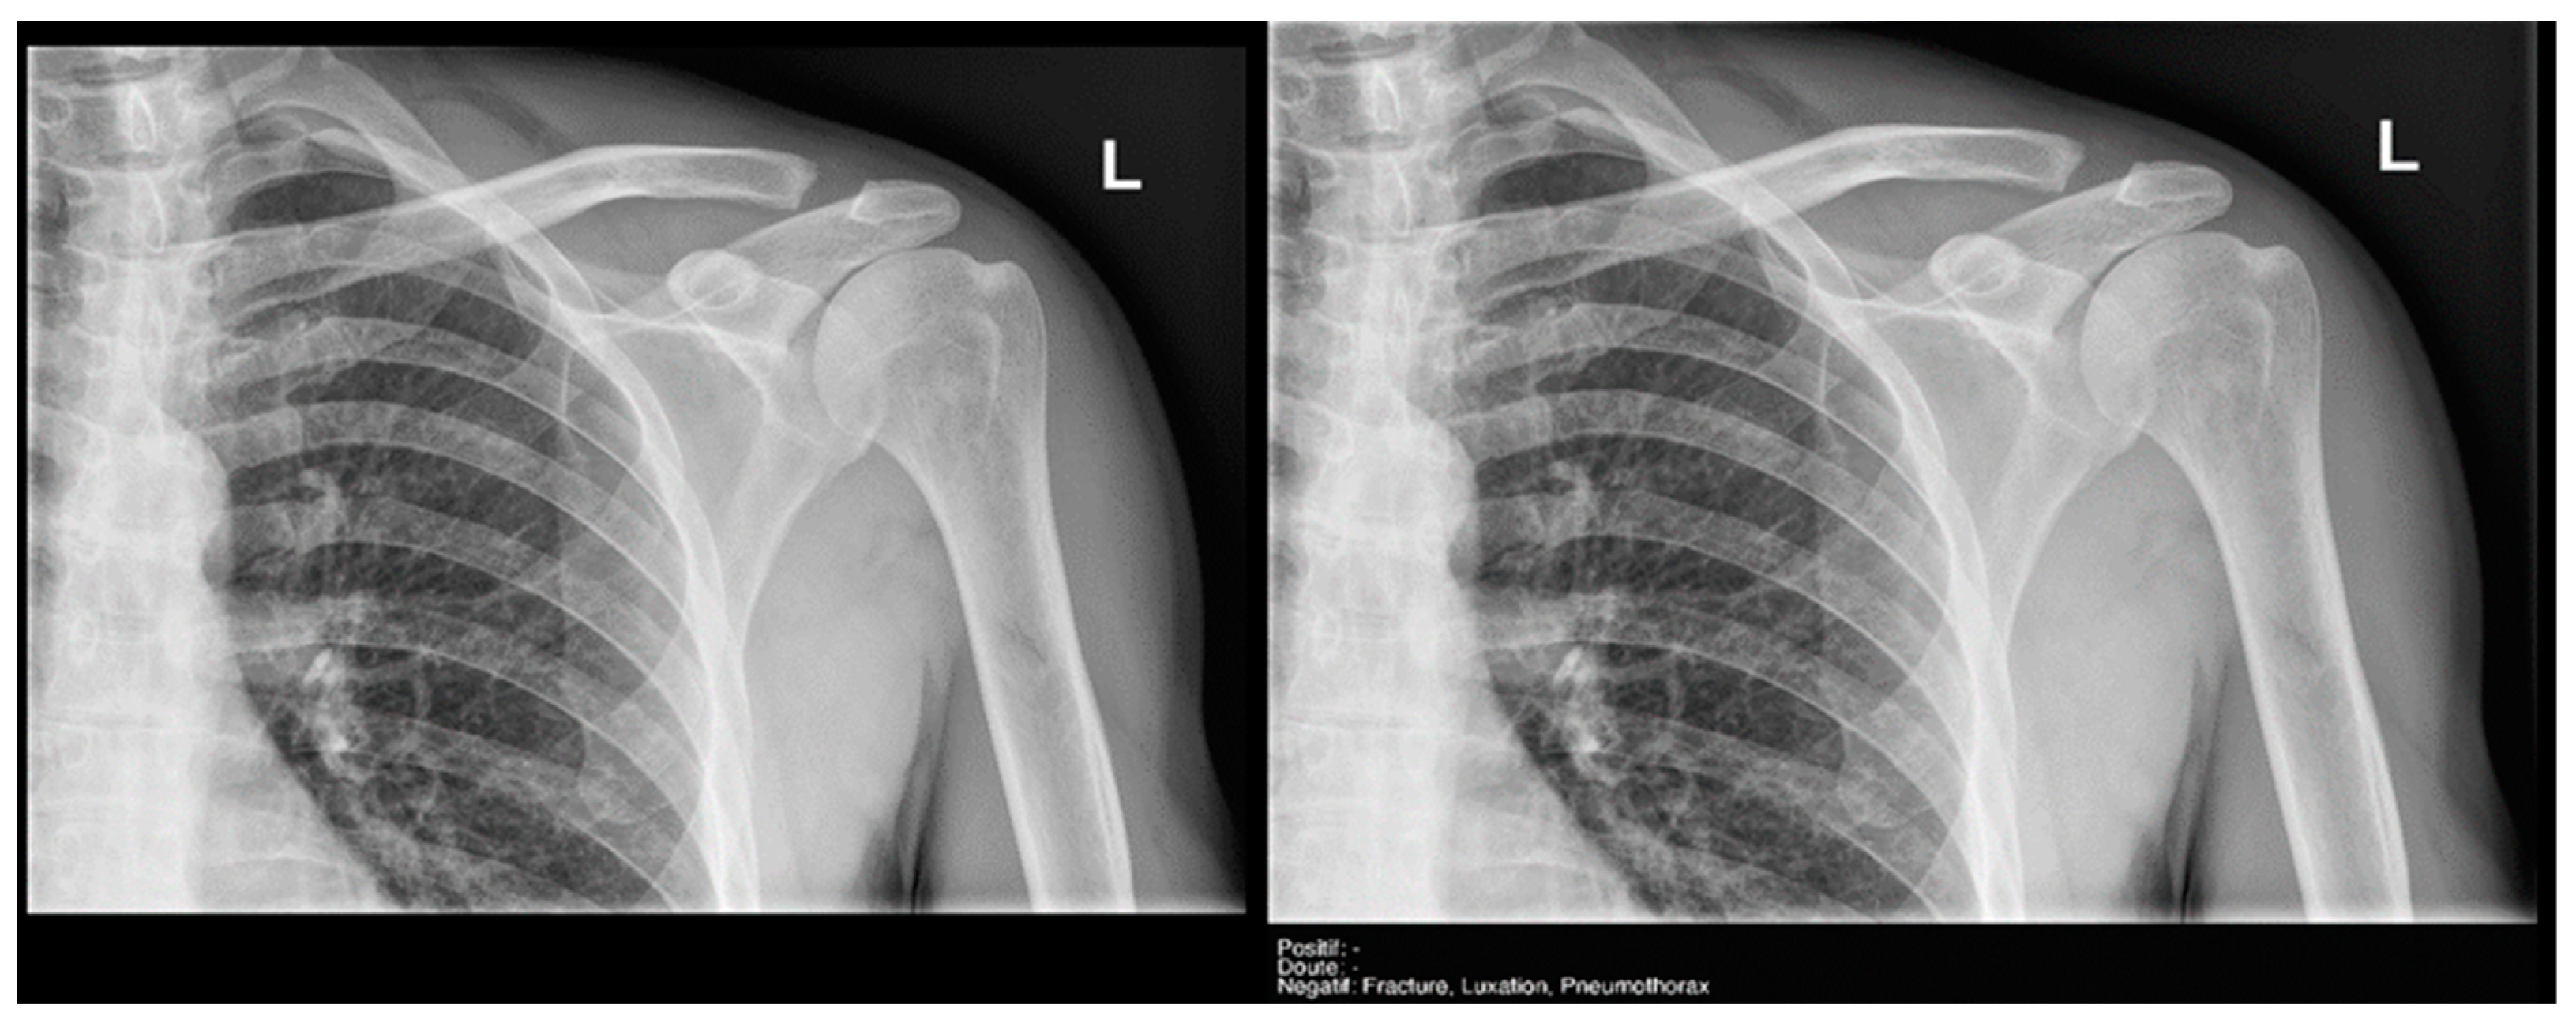

Regarding the detection of dislocations (Table 4), we observed better sensitivity results in the resident’s reading compared to that of the AI, with a high sensitivity of 77.8% in the overall cases, which improved to 84.6% in the large joint group. In contrast, the AI showed lower sensitivity values, with 35% in the overall cases and 35.7% in the large joints. However, specificity values were excellent for all readings and groups, reaching between 99.5% and 100%. (Figure 9 and Figure 10).

Figure 9.

Glenohumeral joint dislocation that was correctly recorded by both the AI and radiology resident.

Figure 10.

Pelvic fracture and coxofemoral dislocation, which was recorded as negative by AI but correctly detected by the radiology resident.

Finally, the specific case of acromioclavicular dislocations is particularly striking, as none of the cases were reported as positive or doubtful by Milvue (Figure 11). We have also not found studies that evaluate the diagnostic capacity of AI in detecting acromioclavicular dislocations. This leads us to propose that future updates of the AI system should focus on expanding the training dataset to include a larger sample of acromioclavicular joint cases, particularly those with pathological conditions, in order to improve the system’s ability to accurately detect these dislocations.

Figure 11.

Acromioclavicular joint dislocation recorded as negative by AI and positive by radiology resident.